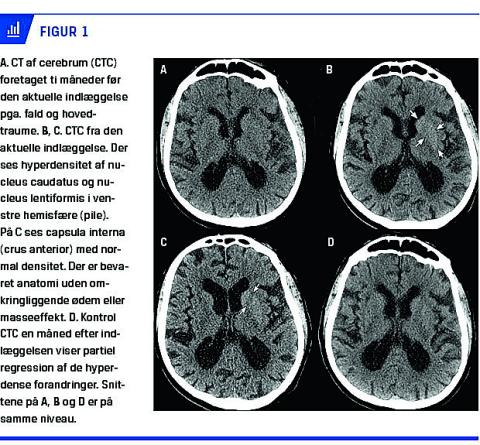

Biokemisk fandt man i det væsentligste upåfaldende forhold fraset et niveau af P-glukose på 17 mmol/l og glykeret hæmoglobin på 152 mmol/mol, hvilket er mere end tre gange den øvre grænseværdi. Der fandtes ingen ketoner i urinen. På mistanke om basalganglieinfarkt blev der foretaget CT af cerebrum (CTC) uden intravenøs kontrast. Skan-ningen viste, at der, siden en tilsvarende undersøgelse var blevet foretaget ti måneder tidligere, var tilkommet hyperdensitet af basalganglierne i nucleus caudatus og nucleus lentiformis i venstre hemisfære (Figur 1 A, B + C). Man afstod fra MR-skanning af cerebrum pga. patientens pacemaker. På grundlag af den kliniske præsentation, de biokemiske resultater og de karakteristiske neuroradiologiske forandringer blev der rejst mistanke om HCHB-NKH.

Patienten fik behandling med tetrabenazin (benzoquinolizinderivat) mod sine hyperkinetiske gener samt hurtigtvirkende insulin efter skema og sidenhen fast antidiabetisk behandling. På denne behandling rettede patientens blodsukkerværdi sig, og overbevægelserne svandt fuldstændig i løbet af seks dage. En kontrol-CTC, som blev foretaget en måned senere, viste partiel regression af forandringerne i basalganglierne (Figur

1D).